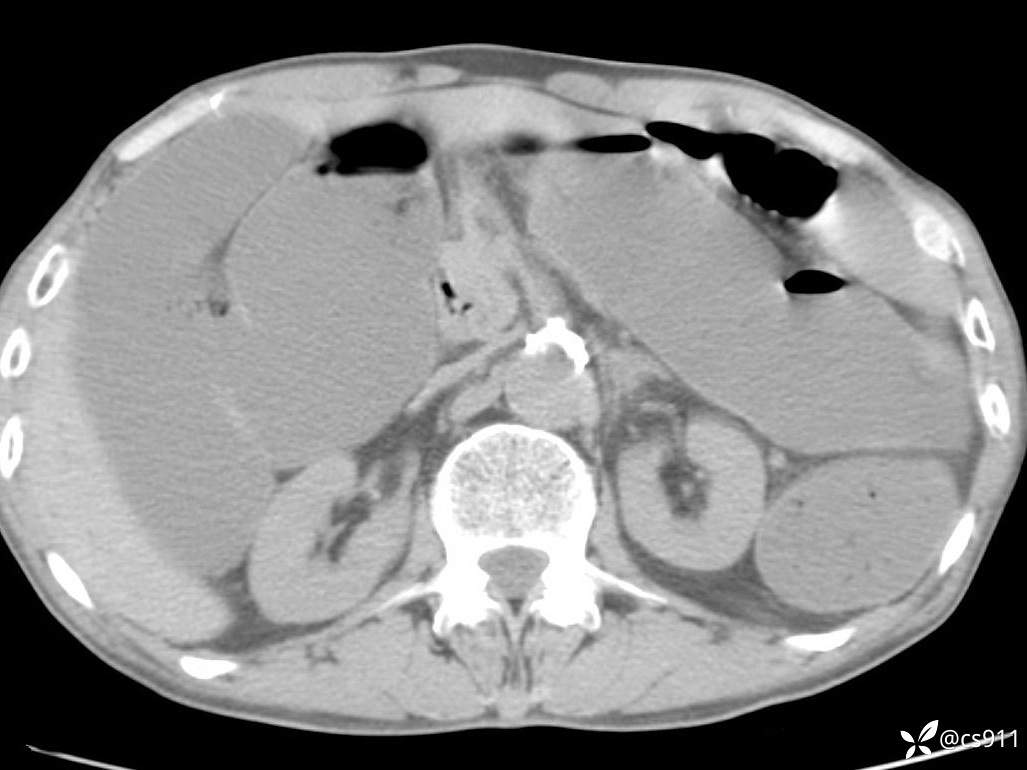

急腹症之急诊CT,原因?答案公布

男,77岁,腹痛、腹胀伴恶心呕吐1天。呕吐胃内容物,非喷射性呕吐,有咖啡色样胃内容物,诉有胃穿孔病史。查体:全腹平,下腹部压痛,全腹无反跳痛,叩诊呈浊音,移动性浊音阴性,肠鸣音减弱,1-2次/分。肛检:直肠未扪及明显肿物,可触及大量粪块。

血淀粉酶(AMY) HH 1859 U/L 35-135